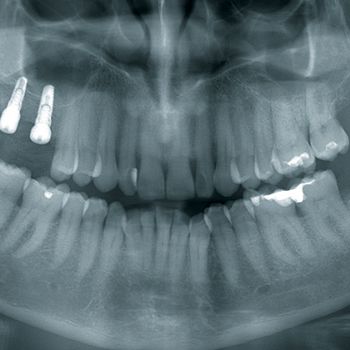

BACK: Wir arbeiten mit unserem eigenen DVT-Gerät. Wir erstellen die Aufnahme des Knochendefekts, besprechen die Situation mit dem Patienten und klären über alle Behandlungsalternativen auf – vom allogenen Knochenblock bis hin zu osteoplastischen Verfahren wie Bonesplitting. Sollte sich der Patient für die Augmentation CAD/CAM-gefertigter allogener Blöcke entscheiden, senden wir die von uns generierten DICOM-Daten an das Unternehmen, das diese Technologie liefert, in unserem Fall ist das Botiss oder Zimmer Dental. Dort wird der dreidimensionale Knochenblock designt.

BLUME: Wir konzentrieren uns auf kompliziertere Indikationen: Frontzahn, schwieriger Seitenzahnbereich im Oberkiefer, schwieriger Seitenzahnbereich im Unterkiefer.